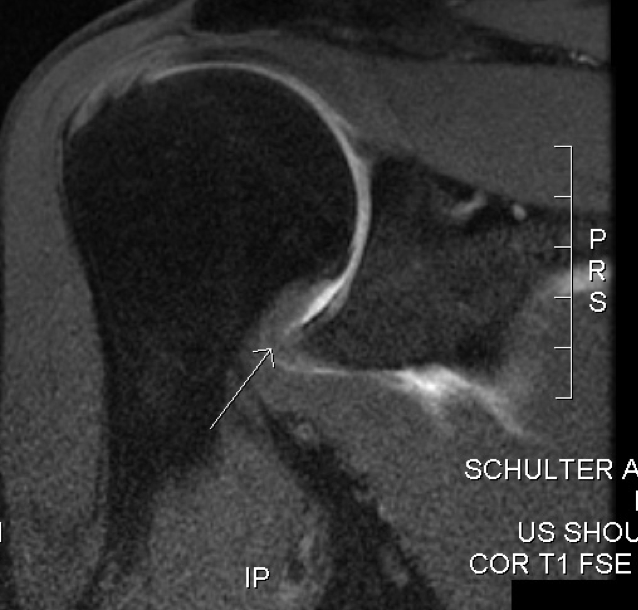

What is shown on the MRI scan?

MRI scan showing thickening of the glenohumeral joint capsule.

MRI imaging can reveal a thickening of the glenohumeral joint capsule in adhesive capsulitis, but also can be used to rule out other conditions affecting the shoulder, such as subacromial impingement syndrome.